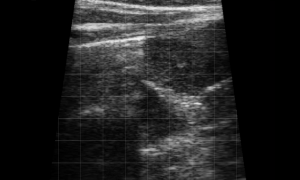

SIMON Ultrasound Database

This ultrasound database is a free resource for students and doctors!

Our collection includes videos of dogs, cats, horses, cows, humans, and many other species!